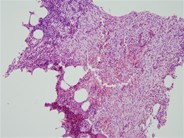

Bone marrow aspirate reveals normal mast cells when stained with May-Grünwald-Giemsa. These mast cells are characterized by their oval or irregular shape and possess a single central nucleus. The nucleus contains densely packed peripheral chromatin. The majority of the cytoplasm is occupied by cytoplasmic granules, which consist of small secretory granules ranging in size from 0.2 to 0.8 micrometers, as well as a few secondary lysosomes. Additionally, the cells exhibit small, finger-like projections extending from the cell membrane. In certain cells, the granules may be dense enough to obscure the visibility of the nucleus. While mast cells share similarities with basophils, their mononuclear morphology and monoclonal antibodies allow for their differentiation.